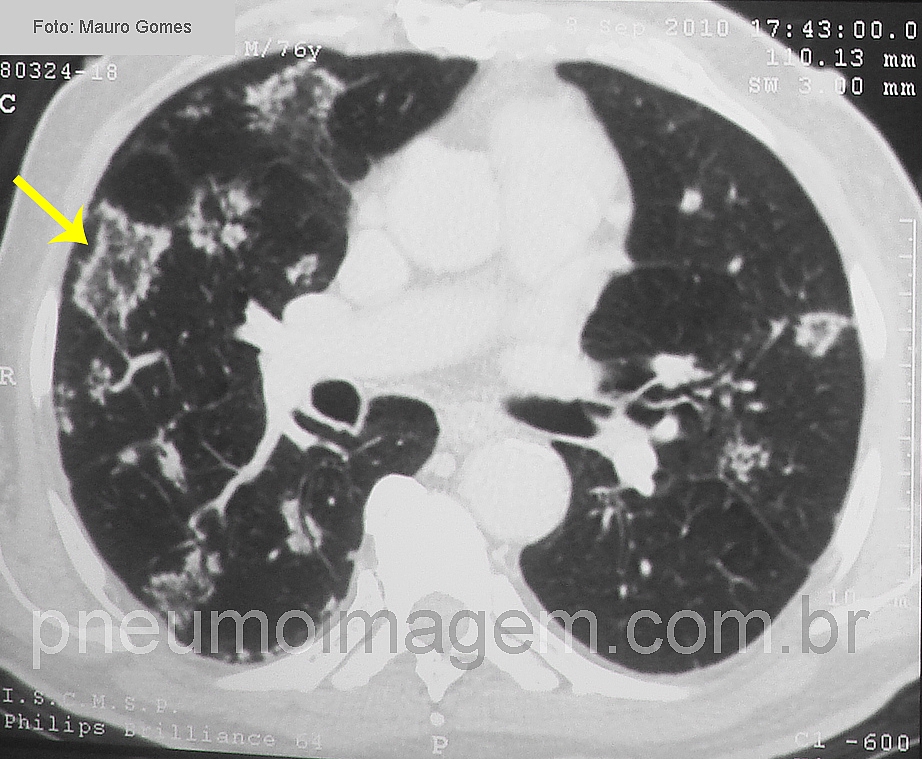

CASO CLÍNICO #31Qual o nome desse sinal e o mais provável diagnóstico a ele relacionado?

What is the name of the sign and the most likely diagnosis related to it?

Sinal do halo invertido. Presente em aspergilose semi invasiva.